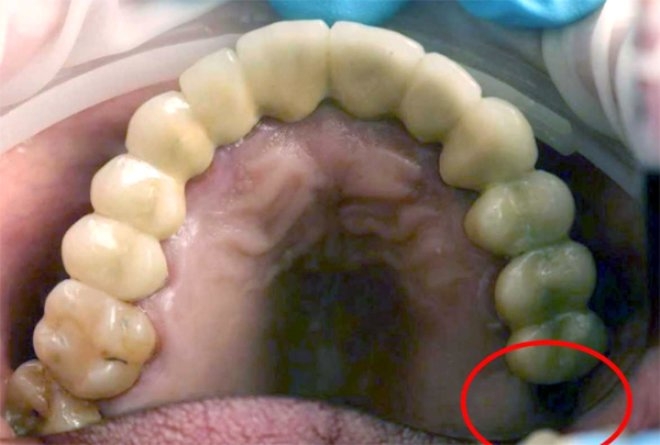

13 yaşındaki çocuğun azı dişi cinsel organından çıktı!

Moskova'daki Morozov Çocuk Hastanesi'ndeki doktorlar, 13 yaşındaki çocuğun testislerinde bir yumruyu tümör sandı, yumru azı dişi çıktı.